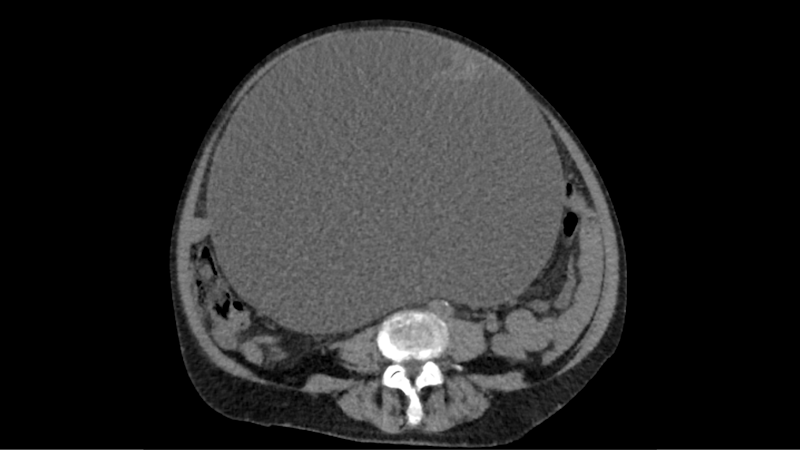

Eine Kärntnerin suchte wegen vermeintlicher Wasseransammlung einen Arzt auf. Doch die Frau hatte kein Wasser, sondern einen riesigen Tumor im Bauch.

Einer 73-jährigen Frau aus Villach hat der Besuch beim Hausarzt wohl das Leben gerettet! Die Kärntnerin hatte laut ORF wegen vermeintlichen Wasseransammlungen im Bauch einen Mediziner konsultiert. Doch eine Untersuchung brachte eine andere Schock-Diagnose, denn die Frau hatte einen Tumor im Bauch.

Die Patientin wurde daraufhin sofort an der Chirurgie des Klinikum Klagenfurt vorstellig, heißt es in dem Bericht weiter. "Wir haben einen 10,2 Kilogramm schweren und 30 Zentimeter im Durchmesser großen Tumor entfernt", erklärt Primarius Reinhard Mittermair, Abteilungsvorstand der Allgemein- und Viszeralchirurgie am Klinikum Klagenfurt dem ORF.

Nach der histologischen Aufarbeitung zeigte sich laut dem Mediziner ein Eierstockkrebs im Frühstadium, der komplett im gesunden entfernt worden ist. "Somit benötigt die Patientin weder eine Chemotherapie noch eine Strahlentherapie", so Mittermair weiter.

Die Frau konnte das Krankenhaus bereits nach fünf Tagen wieder verlassen, berichtet der ORF. Die Patientin möchte anonym bleiben, sagte aber: "Als man nach einer CT-Untersuchung in meinem Bauchraum einen größeren Bauchtumor diagnostizierte, war ich vorerst geschockt, plötzlich verändert sich alles, was macht man in einer solchen Situation?"